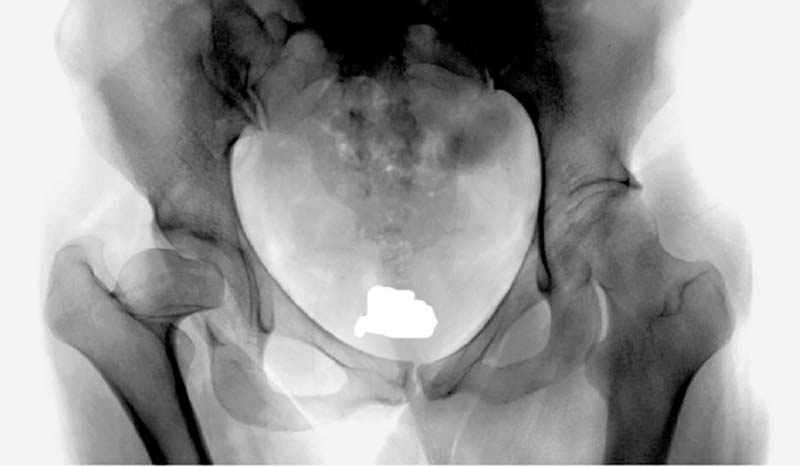

Рис.2 Та же трехмерная модель тазобедренного сустава без аналога связки головки бедра. Пружина динамометра удерживает тазовую часть модели от опрокидывания, поддерживая стабильность так же, как отводящие мышцы обеспечивают ее в отсутствии связки головки бедра.